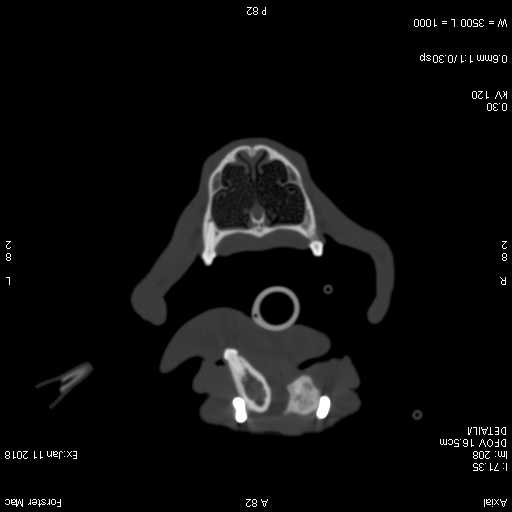

Two months after the reconstruction a follow up CT-scan was performed which demonstrated good new bone formation and a complete bridge between the ends of the bone resection. There was no evidence of screw loosening.

Fig. 3: Transversal view of a CT scan showing new bone formation after mandibular reconstruction.